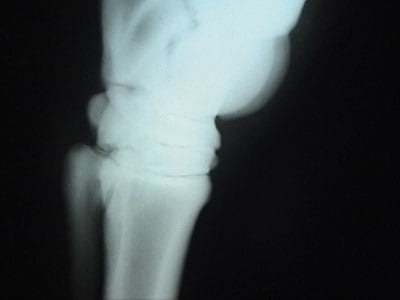

Fig. 2. La imagen de la izquierda muestra como se toma una radiografía con puntos de referencia. La imagen central muestra la rotación de la falange, el espacio donde se presenta la separación laminar y la necrosis de la palma. En la imagen de la derecha hay una rotación que casi llega a la vertical (equino del video) con deformación de la tercera falange y signos de osteomalacia.